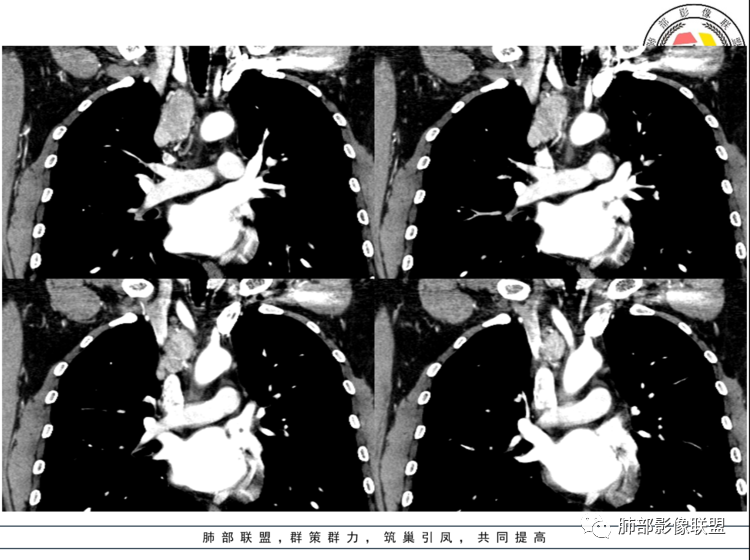

男,40岁,体检发现纵隔占位

•查血常规、血生化、肿瘤标志物、尿常规大致正常。气管腔静脉间隙团块状影,密度均匀,边界清楚,增强扫描,明显的强化,肿块的周围气管旁见多个肿大的淋巴结,强化特点类似。考虑良性占位,巨淋巴增生症。需要与异位胸腺瘤、结节病、淋巴瘤、副神经节瘤、淋巴结转移瘤鉴别。

中年男性右上纵隔椭圆形软组织肿块,边界清,密度均匀,明显均匀强化(峰值在动脉期),周围见小血管影进入及有小淋巴结,考虑CD>副节。

纵膈内上腔静脉内后方肿块,边缘清晰,形态不规则,周围可见多发小淋巴结,明显强化。纵膈内强化明显的常见有CD,异位甲状腺,副节瘤,血管瘤。异位甲状腺平扫密度高一些,钙化常见,不符。副节瘤好发生于后纵膈、主动脉旁、肺动脉旁、心包内,而且容易坏死,一般沿神经节分布,纵径大于横径。综合考虑:CD>副节瘤。

40岁,男性。右中上纵隔见实性团状软组织影,密度均匀,边界光整清晰,与周围结构分界清晰,增强后动脉期明显均匀强化,静脉期延迟期强化逐渐减低。定性:良性病变或肿瘤,常规考虑巨淋巴结增生CD,需鉴别诊断的疾病有1神经源性肿瘤如神经鞘瘤,沿纵轴生长,横轴大于纵轴,但一般有AB区,有囊变坏死,多见后纵隔,强化渐进性强化,发生前中纵隔的恶性程度高,此例不太支持,但不排除;副神经节瘤,囊变多见,不支持;节细胞瘤,一般纵轴大于横轴,不支持;2神经纤维瘤SFT,蛇蚊征,待排,3孤立性转移瘤,少见,一般有原发肿瘤病史,肿瘤标志物异常,环形强化,不支持。4淋巴瘤,常多发淋巴结肿大,少见囊变坏死,待排。5异位甲状腺,一般平扫密度较高,此例不支持。

中年男性,上纵隔气管旁软组织肿块,边界清楚,与周围结构脂肪间隙存在,长轴与气管一致,增强明显不均匀强化,静脉期及延迟期强化稍减退。强化明显的纵隔肿瘤,考虑CD,鉴别副神经节瘤。淋巴瘤强化不符合,神经鞘瘤没看到明显的A区、B区,暂不考虑。

3.1单发型CD的肺部表现

单发型CD多为透明血管型,所以明显强化和中央分枝状钙化具有特征性。在CT上表现圆形或类圆形软组织密度影,伴或不伴周围淋巴结增生,体积一般较大,边缘光整,病灶中央的弧形、线样、分枝样及枯枝样钙化(因为肿块内增生的血管组织玻璃样变或退变后钙盐沉积,故多呈血管样铸型的分支状或枯枝状);透明血管型因为其内血供丰富,周围可见粗大的供血动脉,在多期扫描动脉早期明显强化,强化程度与大血管相仿,又由于病灶内血管壁玻璃样变或纤维化及内皮细胞过度增生致血管腔狭窄,对比剂退出减慢,故延迟扫描扫描仍可持续强化,呈“早进晚出”的强化方式。因为其血供丰富,坏死、囊变或出血少见,但是有时候病灶内灶状或条片状低密度影,是纤维组织或发生玻璃样变性的血管结构,而不是缺血坏死区。